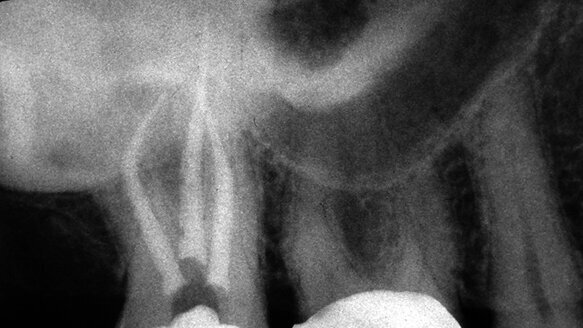

Given the complex pulpal anatomy that exists, more conservative preparations that limit instrumentation to conical shapes tend to leave a good deal of debris in the extensions of what are often asymmetric, highly oval canals (Fig. 2). Both relieved and unrelieved K-reamers, whether used manually or in a reciprocating handpiece, can be used more aggressively and without fear of breakage against the lateral walls of oval canals, from the thinnest instrument onwards.

Figures 3 through 8 are examples of several of the more complex cases we have shaped using relieved and unrelieved K-reamers both manually and in the 30-degree reciprocating system. We are cleansing these canals to a greater extent because the imposition of breakage does not apply. We are purposely working all the walls of highly oval canals because centering is not a requirement for safe usage. Greater preparation of canals assures superior irrigation and its activation by using the 30-degree reciprocating handpiece as a sonic source of energy accomplishing two tasks at the same time.